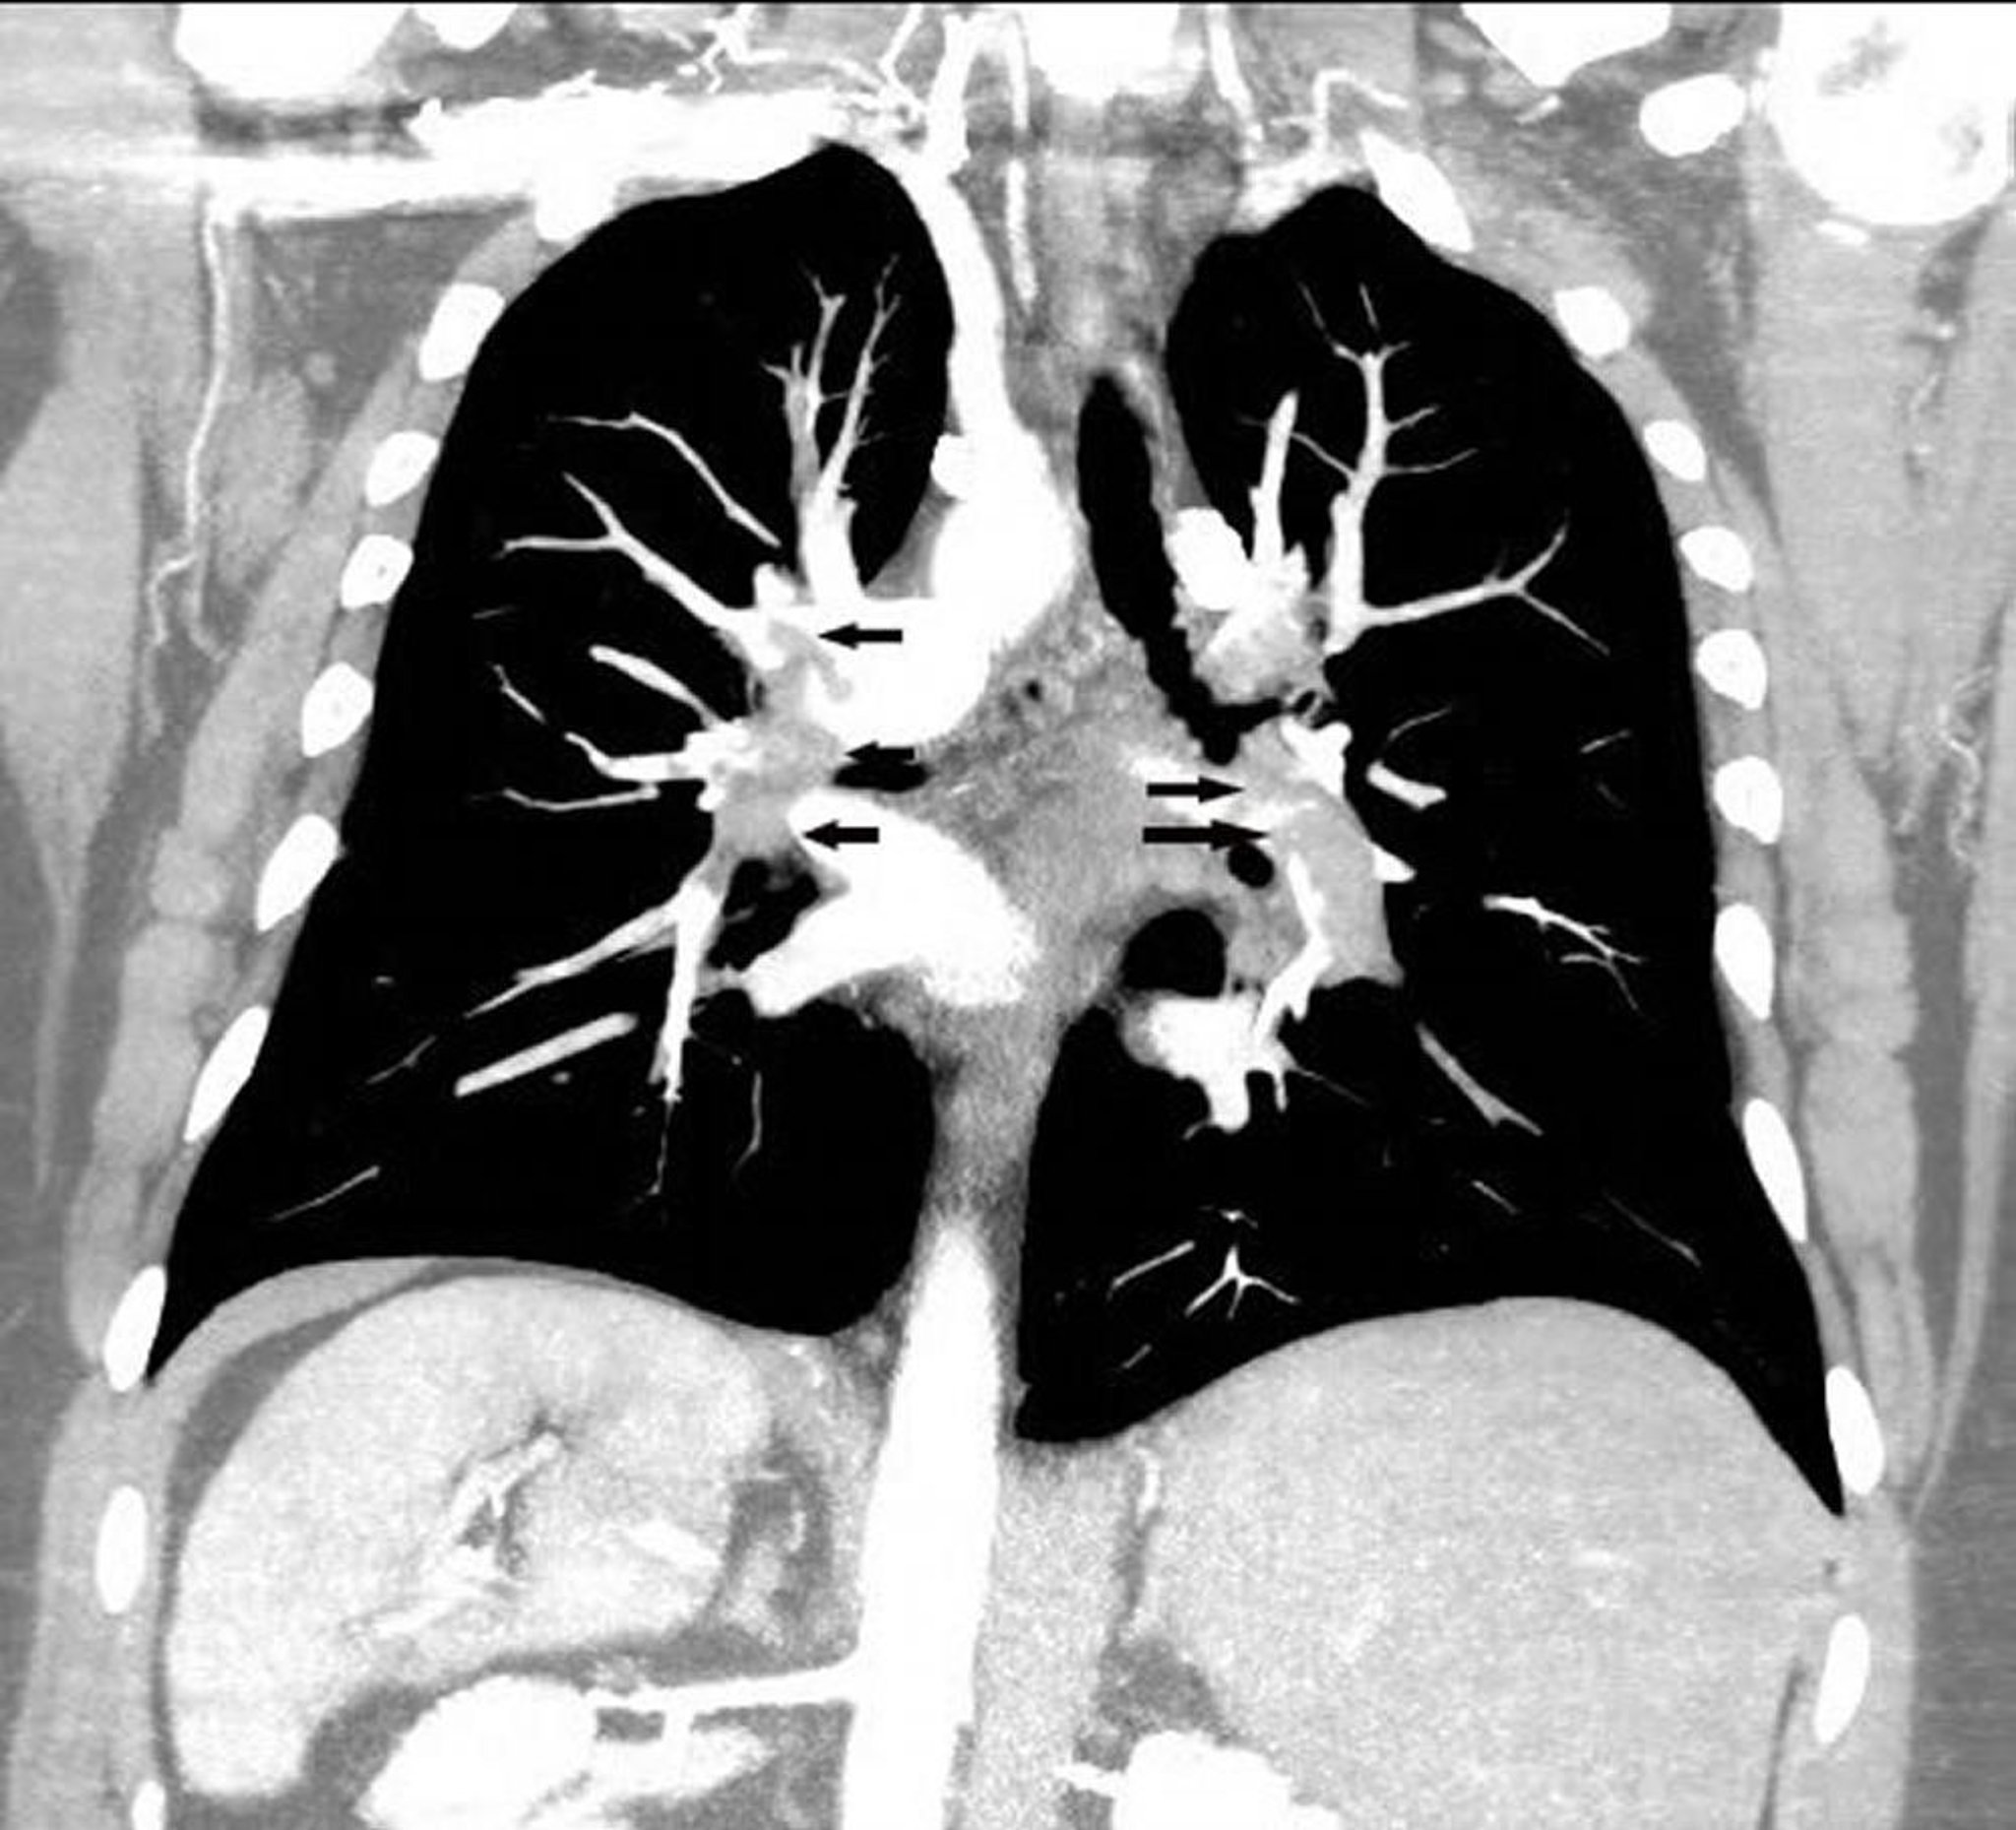

Coronal Reconstruction CT Pulmonary Angiography

Coronal reconstruction CT pulmonary angiogram shows an extensive pulmonary embolus in both pulmonary arteries (arrows).

Image courtesy of Hakan Ilaslan, MD.